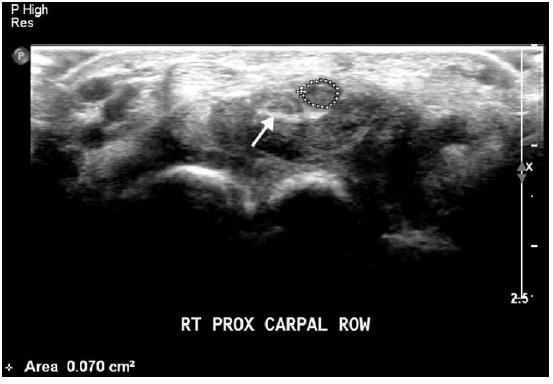

A rare case of carpal tunnel syndrome caused by a thrombosed persistent median artery is presented here.

The diagnosis was delayed due to the overlapping cervical radiculopathy. Acute severe pain and nocturnal paresthesia were chief complaints. Ultrasonography, magnetic resonance imaging, and computed tomography angiography revealed that the median nerve was compressed by the occluded median artery. Instead of surgery, conservative therapy was tried. It worked well for six months.